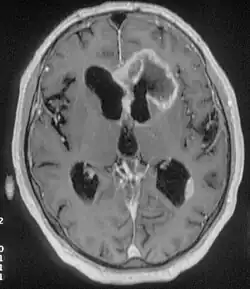

Zespół czołowy (łac. syndroma frontale, ang. frontal lobe disorder) – zespół objawów psychoorganicznych związanych z uszkodzeniem okolicy czołowej mózgu, najczęściej przez guz. W czystej postaci wiąże się z uszkodzeniem kory płatów czołowych. Towarzyszyć mu mogą objawy niezwiązane z uszkodzeniem kory i niewchodzące w skład obrazu klinicznego zespołu, np. związane ze wzrostem ciśnienia śródczaszkowego lub uszkodzeniem innych części mózgowia przez proces rozrostowy.